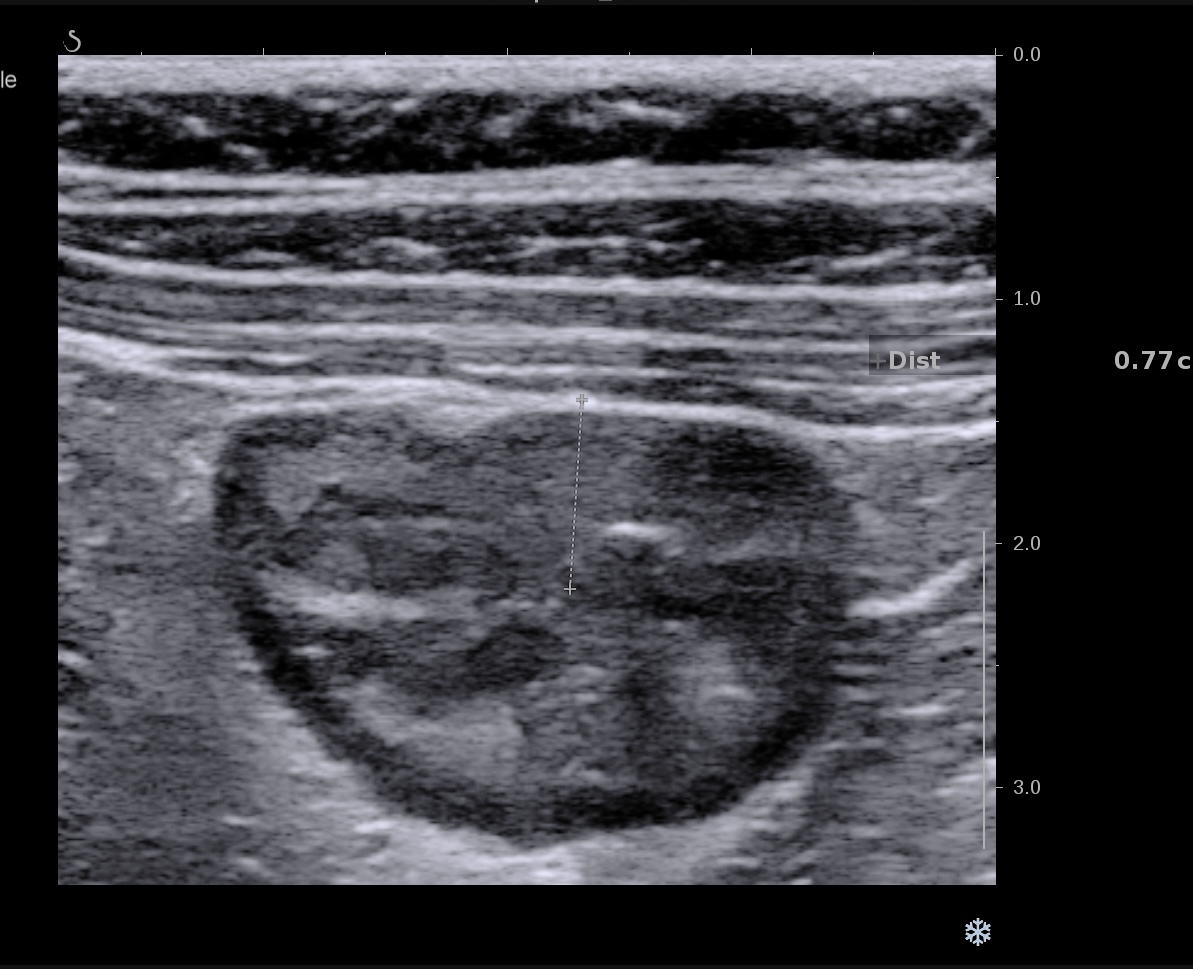

Patiente revue 4 ans plus tard sous vedolizumab Entiyo® en rémission clinique complète, biologie et calprotectine fécale normales, l’échographie (mauvaise échogénicité de la patiente) montre une paroi normalisée entre 1,8 et 2,8 mm d’épaisseur structure en couche conservée.

Le score de Milan MUC est à 3.92 confirmant la rémission échographique